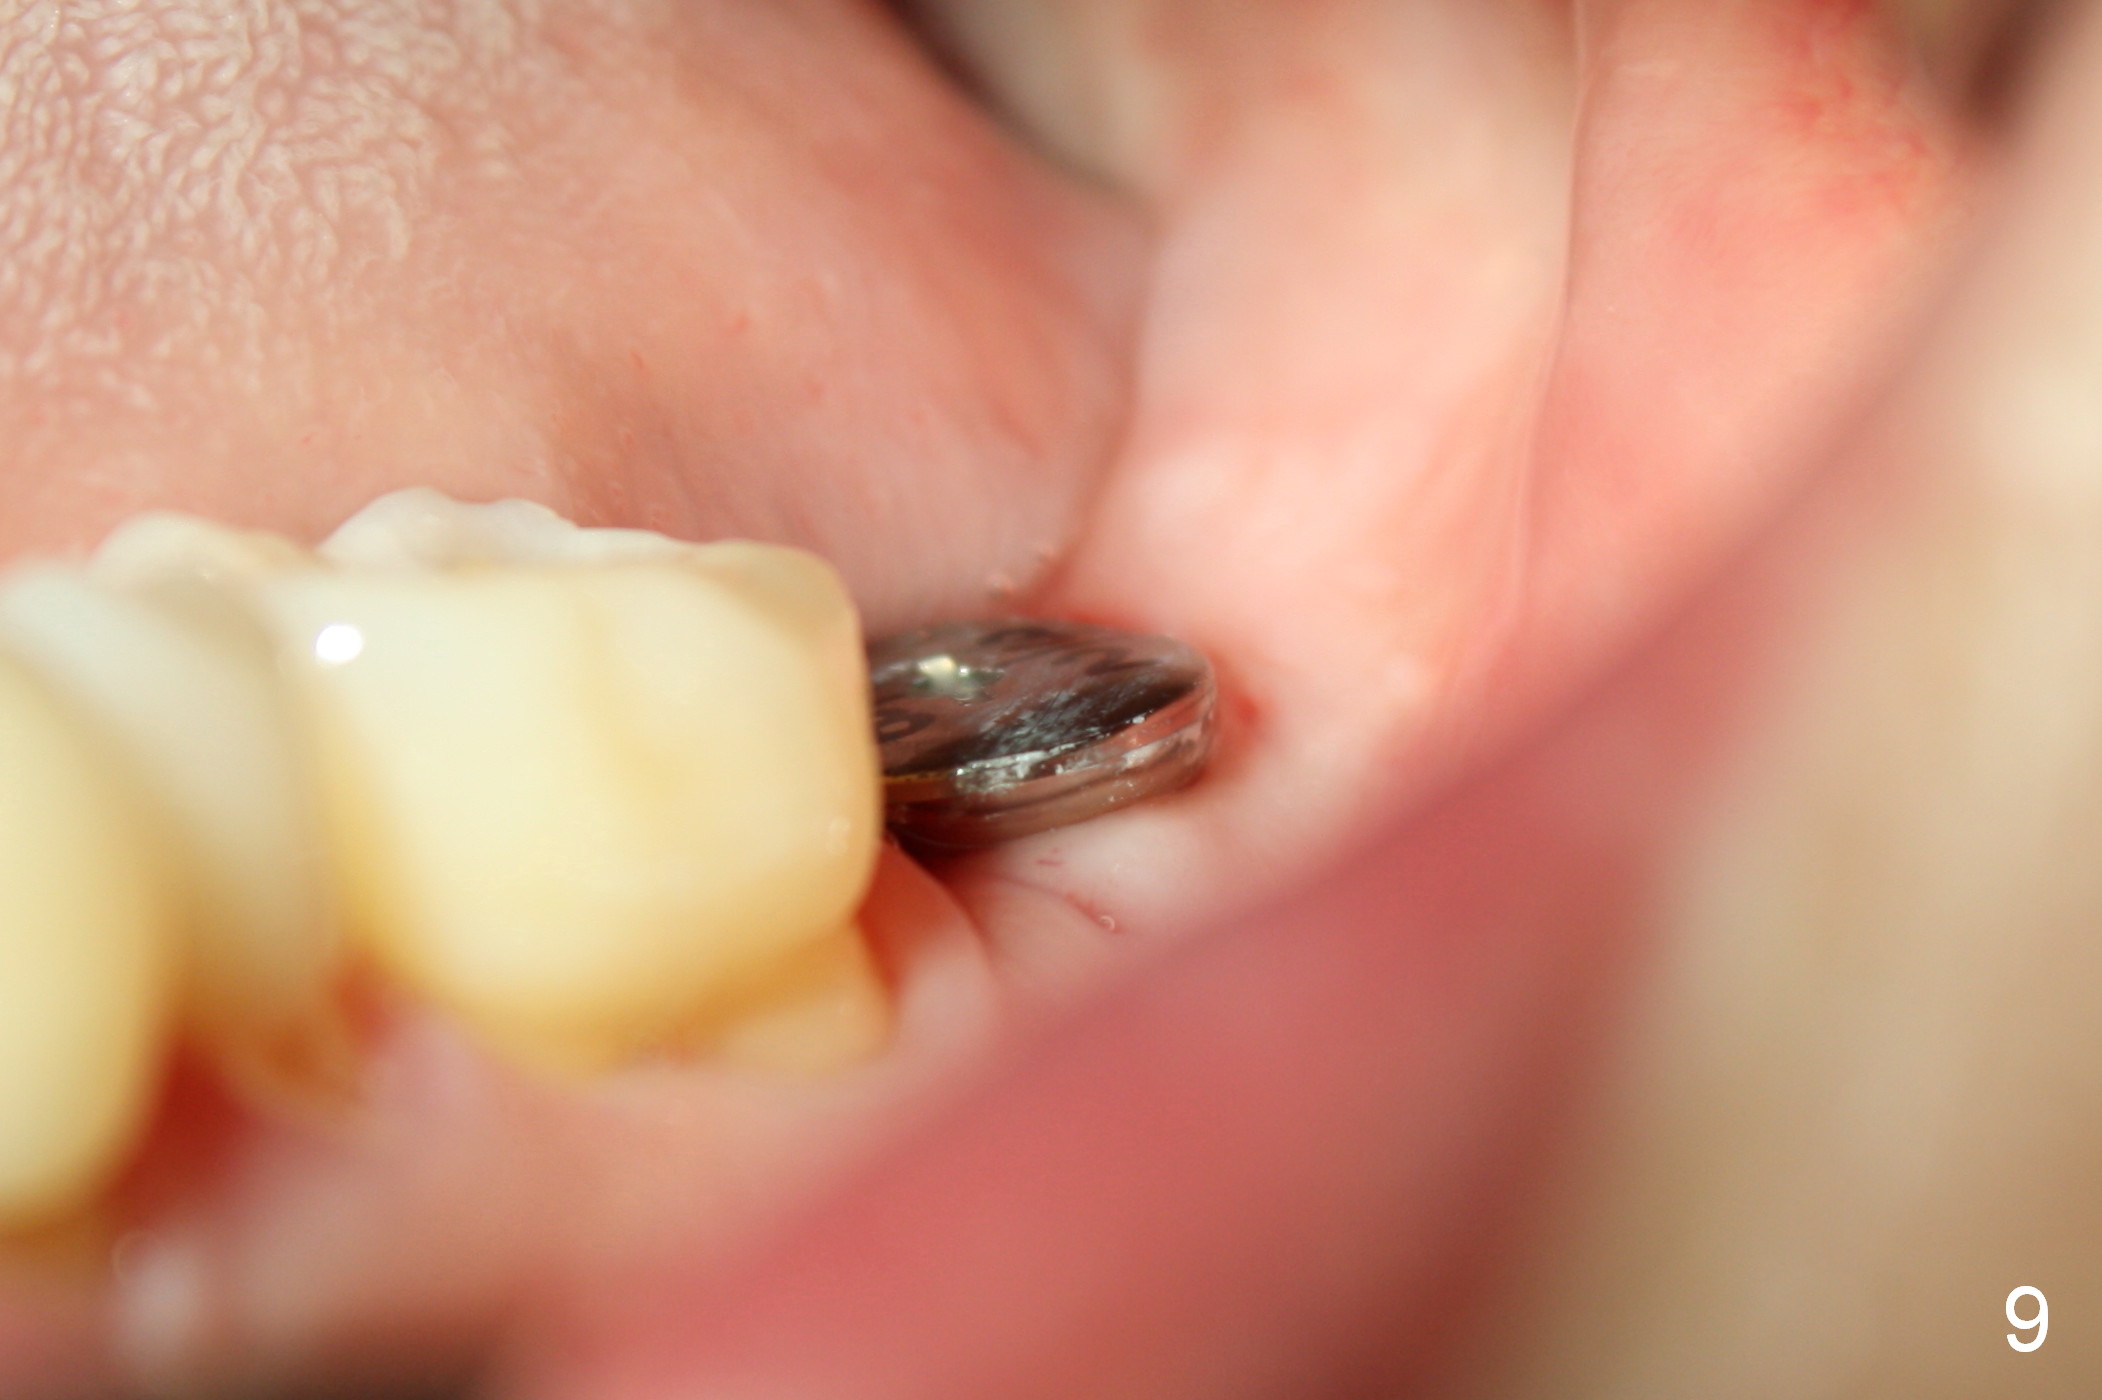

A 48-year-old lady is a dental phobic, requesting extraction of the lower left 2nd molar (Fig.1). She returns for implant placement 9 months post extraction (Fig.2). The ridge is mildly to moderately atrophic. It appears that a 5x12 mm implant is appropriate for the site (Fig.3). For safety, osteotomy is initiated at the depth of 10 mm; it appears that there is enough height for a 12 mm implant (Fig.4). The depth is controlled by drill stopper (Fig.5 S). Finally a 5x12 mm implant is apparently safely placed (Fig.6). A healing abutment is placed and the incision is sutured with 4-0 Chromic gut (Fig.7). Perio dressing is applied around the healing abutment for wound protection (Fig.8). It appears that the healing abutment (Fig.8': *) helps stabilize the perio dressing, which remains in place 1 week postop. When the perio dressing is removed, the wound around the healing abutment is healing (Fig.9). There is no bone loss around the implant 3 months postop (Fig.10 (H: healing abutment), or 16 months postop (i.e., 9 months post cementation, Fig.11,12). The patient complains of pain when she chews with the implant crown, but pain stops whenever she does not bite. Percussion does not elicit any discomfort. The gingiva is healthy. There is possibility of the buccal plate being thin or the lingual plate being perforated in the submandibular fossa. If the discomfort remains the same next 6 months, CBCT will be prescribed.